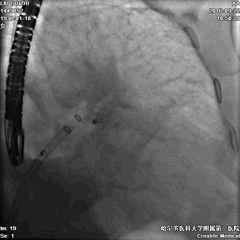

手术过程—全麻下食道超声结合DSA指导房间隔穿刺

穿刺点选择中间略偏后下位。

穿间隔后,给予肝素7000u,测得左房压力12mmHg。